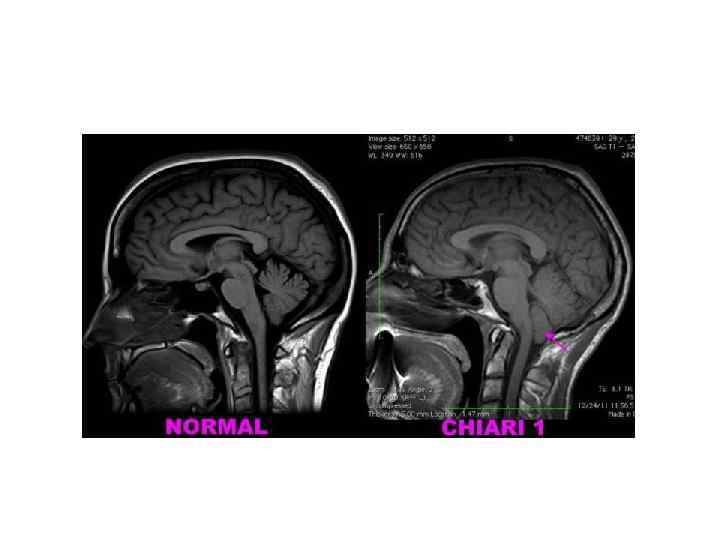

Мальформация Арнольда-Киари https: //commons. wikimedia. org/wiki/File: Chiari 2. jpg? uselang=ru